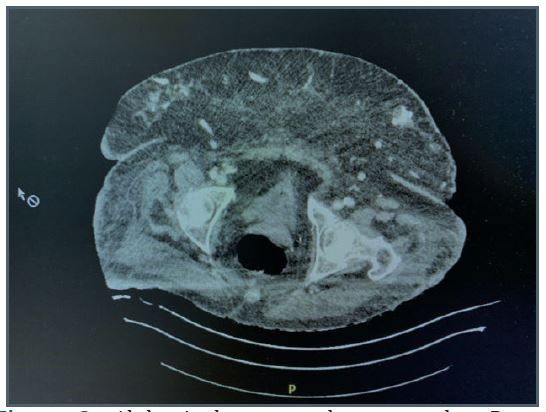

Figure 2: Abdominal computed tomography: Deep collection in subcutaneous fat corresponding to area of necrosis.

The patient’s medication regimen included Simvastatin®, L-thyroxin®, Pantomed®, etercalcetide, calcitriol and enoxaparin. A subsequent abdominal CT revealed a deep collection within the subcutaneous fat in contact with the muscular wall with high density, corresponding to an area of necrosis (Figure 2).